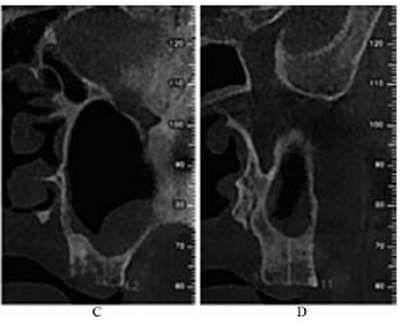

治療過程:左側(cè)上頜局麻下,于25~28牙區(qū)作梯形切口,翻瓣。用直徑6mm的去骨環(huán)鉆于25牙遠(yuǎn)中根尖處開窗,去除游離骨片,見竇膜完整,剝離竇膜。從開窗處穿刺抽出約2mL淡黃色粘稠液體,生理鹽水加慶大霉素沖洗竇腔至沖洗液清亮,竇膜穿孔處放1.5 cm×2.5 cm膠原膜1片,在竇底與膠原膜之間植入骨粉1g,開窗表面覆蓋2 cm×2.5 cm膠原膜1片及富血小板纖維蛋白膜3片,減張縫合(圖2)。

圖2 上頜竇外提升術(shù)中。注:A,開窗;B,抽出液體;C,植入骨粉;D,縫合。